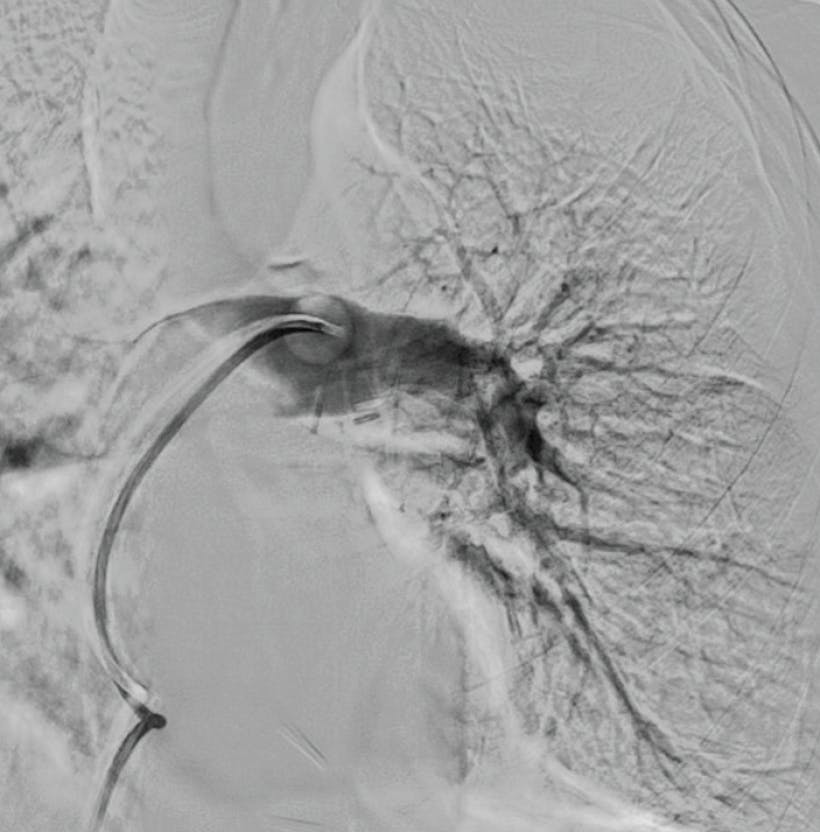

Postprocedure angiography demonstrated resolution of thrombus within the left upper and left lower lobes. The estimated blood loss was minimal at 70 mL. Hemostasis achieved with a purse string suture secured with a three-way stopcock. The access-to-closure procedural time was 31 minutes with a total thrombectomy suction time of 1 minute. The patient was transitioned from high-flow nasal cannula on the procedural table and weaned to room air over the next 2 days. He was discharged from the hospital on postoperative day 3 on appropriate oral anticoagulation.

Figure 2. Postprocedural angiogram of the left PA.